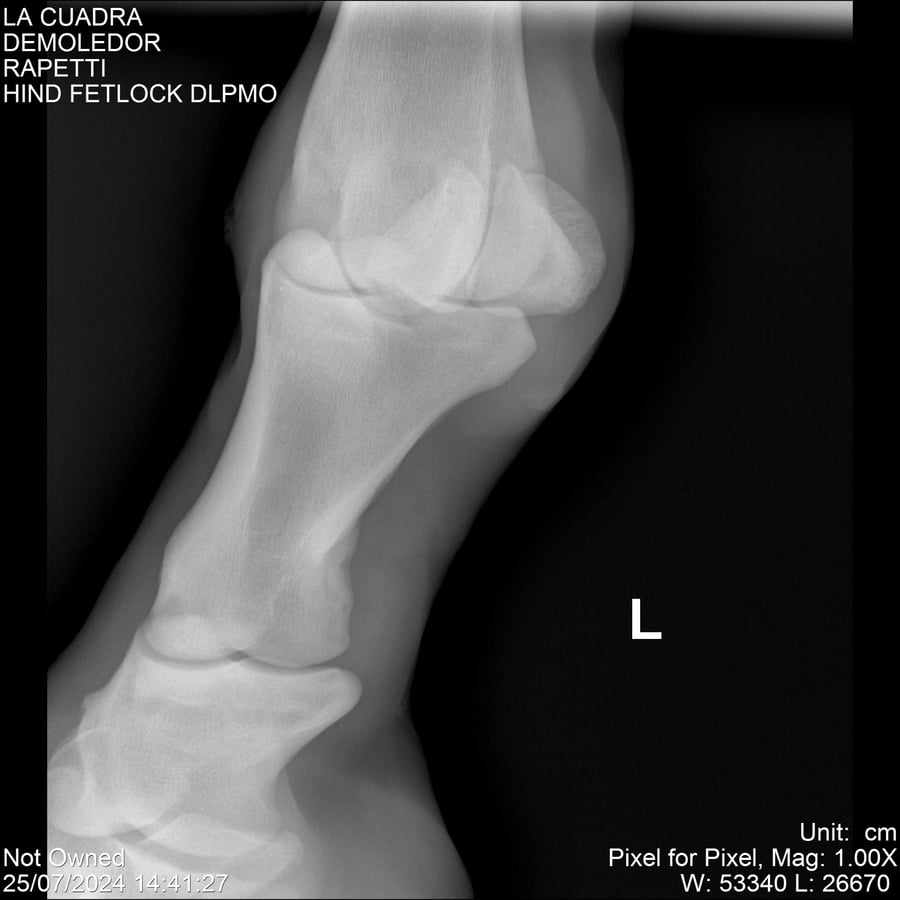

LOTE 14, DEMOLEDOR 🔥 🔥 🔥 Lote Anterior Volver al remate Lote Siguiente Ficha Contacto Montevideo - Ficha del Lote Identificador: #284454 Categoría: Yeguarizos Montevideo - 89 Visualizaciones ClicData Contacto Empresa: Abelenda N. R., Walter Hugo Nombre*: Teléfono* : E-mail* : Mensaje Enviar Registrese gratis Este contenido Exclusivo está disponible sólo para usuarios registrados Ingresar